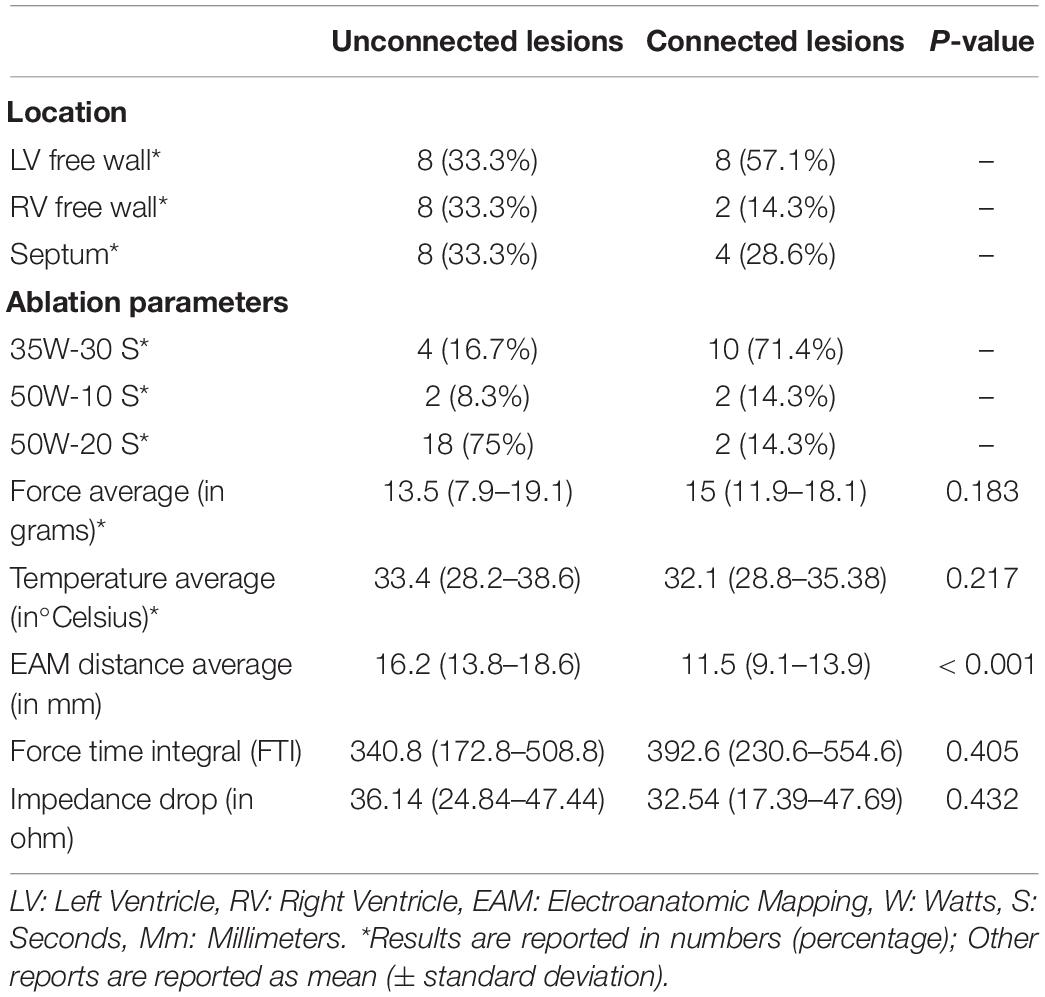

Out of the 81 lesions, we performed thirty-eight paired ventricular lesions. A total of twenty-four unconnected (twelve pairs) lesions were created and equally distributed in the left ventricle (LV), right ventricle (RV) and septum. A total of fourteen connected lesions were created (seven pairs), eight of which are in the LV. There was no significant difference in force and temperature used in both groups (p > 0.05). However, there was a significant difference in EAM distance between connected and unconnected lesions (p < 0.05).

All characteristics of the paired lesions are summarized in Table 1. A flow chart summarizing the study is seen in Figure 1.